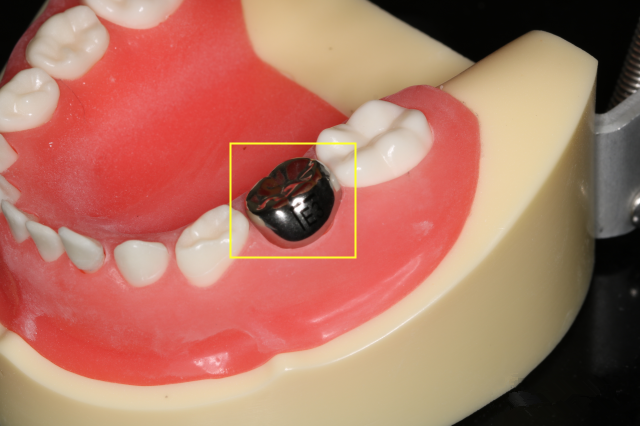

给孩子的患牙再增加一层保护伞——预成冠

儿童乳牙的保护伞——“预成冠”

乳牙预成冠是通过预先加工成型,嵌套在儿童乳磨牙上(儿童初次长出,用于磨碎食物的牙齿)的人工牙冠。用来恢复乳磨牙的外形、咀嚼功能和咬合关系。